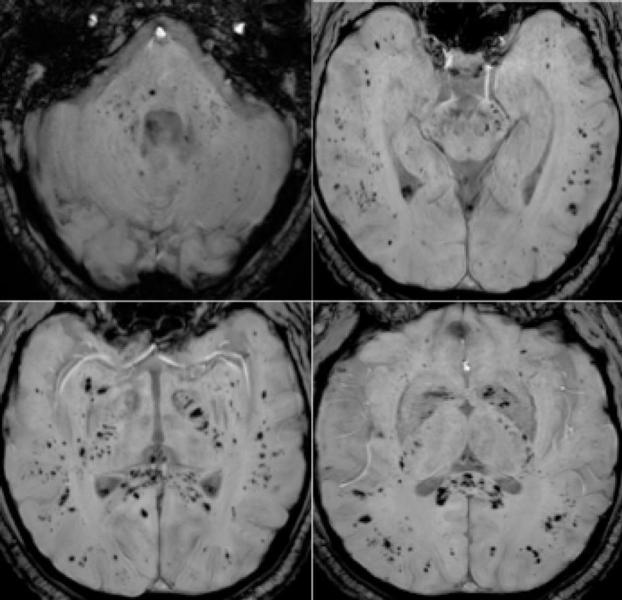

Among the 37 patients included, 28/37 (76%) were associated with one neuroimaging pattern, 7/37 (19%) with two patterns, and 2/37 (5%) showed three patterns. The most frequent MRI findings were: signal abnormalities located in the medial temporal lobe in 16/37 (43%) patients, non-confluent multifocal white matter hyperintense lesions on FLAIR and diffusion sequences, with variable enhancement, with associated hemorrhagic lesions in 11/37 patients (30%), and extensive and isolated white matter microhemorrhages in 9/37 patients (24%).